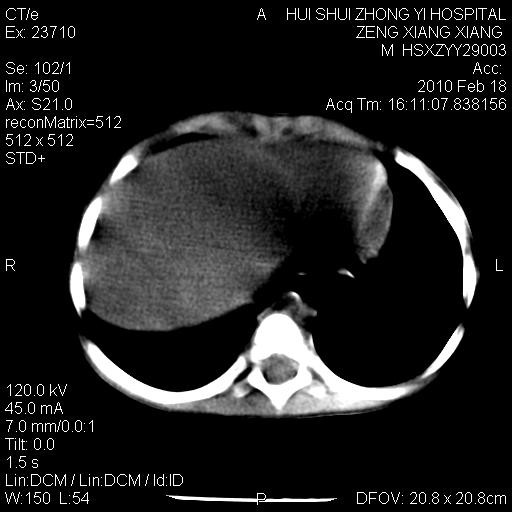

标题: PED3106:男,2岁,腹胀1月。 [打印本页]

标题: PED3106:男,2岁,腹胀1月。

定位腹膜后,肾上腺来源;

定性:恶性神经源性,肾上腺神经节母细胞瘤可能性大。

鉴别:肝母、肾母、肝脏中胚层错构瘤。

依据:年龄、有钙化,肾脏及肝脏受压移位。

肝母细胞瘤可能性大,右肾形态大体可见,不支持肾母细胞瘤,右肾移位不明显,肾上腺神经母细胞瘤可能性不大。